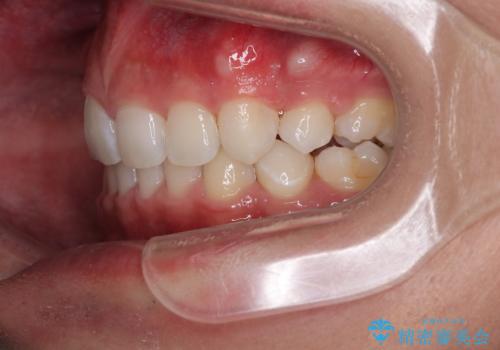

治療後には、デコボコと正中の位置が改善し、見た目だけでなく歯磨きがしやすい清潔なお口の環境を手に入れました。